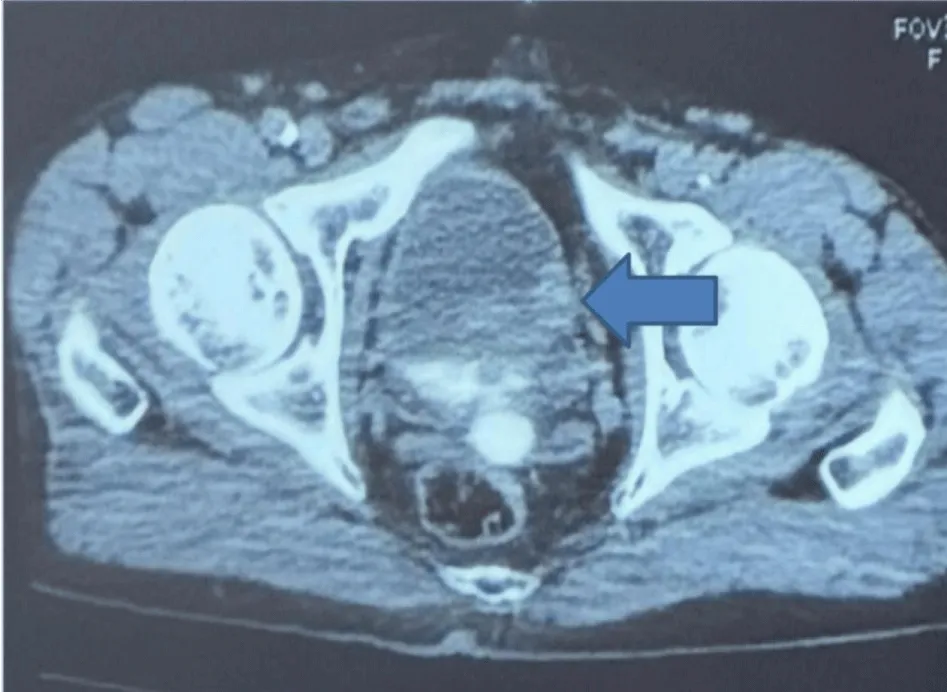

Subsequent contrast-enhanced CT, performed during portal and excretory phases, confirmed a well-circumscribed soft tissue mass measuring 3.0 × 2.6 cm with homogenous enhancement and no signs of perivesical fat invasion. The lesion was located on the left lateral wall, distinct from the ureteral orifice and the bladder neck, explaining the absence of upper tract dilatation (Figure 2).

Figure 2: Computed Tomography Findings. Axial contrast-enhanced CT scan confirming a well-circumscribed intravesical soft tissue mass measuring 3.0 × 2.6 cm with homogenous enhancement and no signs of perivesical fat Invasion. The lesion was located on the left lateral wall, distinct from the ureteral orifice and the bladder neck, explaining the absence of upper tract dilatation.